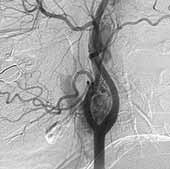

Характерным рентгенологическим признаком невриномы слухового нерва при рентгенографии в проекции Стенверса является расширение внутреннего слухового прохода, изменение его формы (чаще отмечается веретенообразность) (Рис. 1). К признакам опухолевого роста относится также изменение очертаний кортикального слоя кости, ограничивающего просвет прохода — появление эррозий, узур, стертости контура. К ним относится и асимметричность изображения поперечного гребня в области дна прохода. При значительном экстрамеатальном распространении опухоли могут наблюдаться дефекты пирамиды в области внутреннего слухового отверстия. Участки разрушения костной ткани при невриномах имеют, как правило, гладкие и четкие очертания. КТ — признаками опухоли слухового нерва являются: расширение слухового прохода, наличие округлого, реже овального объемного образования, зачастую с очагами кистозной дегенерации и хорошей реакцией на усиление, острый угол между поверхностью опухоли и задней поверхностью височной кости.

[Увеличить]

Рис. 1. Невринома слухового нерва. На рентгенограмме вичочной кости в проекции Стенверса имеется расширение внутреннего слухового прохода справа.